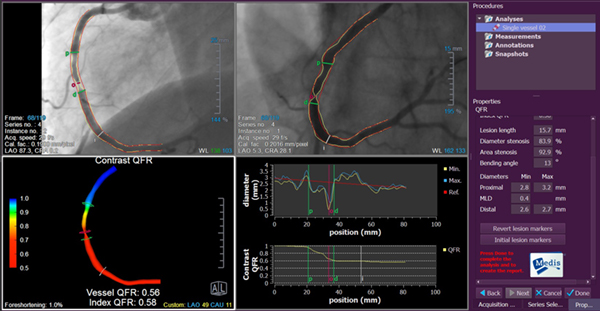

・冠動脈疾患の機能的虚血評価をアンギオ画像のみで簡便に行えることで注目を集める

「3D心血管アンギオ画像解析システムQAngio XA 3D(QFR)」

※QAngio XA 3Dは学術研究用プログラムです。臨床診断の目的では使用出来ません。